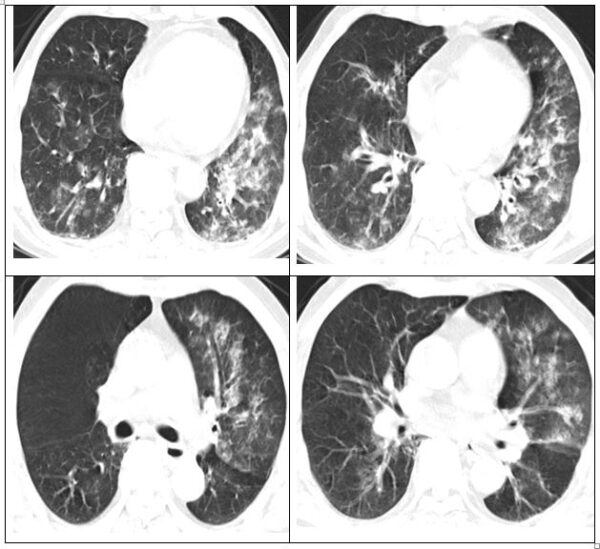

Hình ảnh phổi của người bệnh bị viêm lan tỏa và đông đặc.

Bệnh nhân đã được khám và làm cận lâm sàng: test cúm A dương tính, CT ngực viêm phổi lan tỏa và đông đặc.